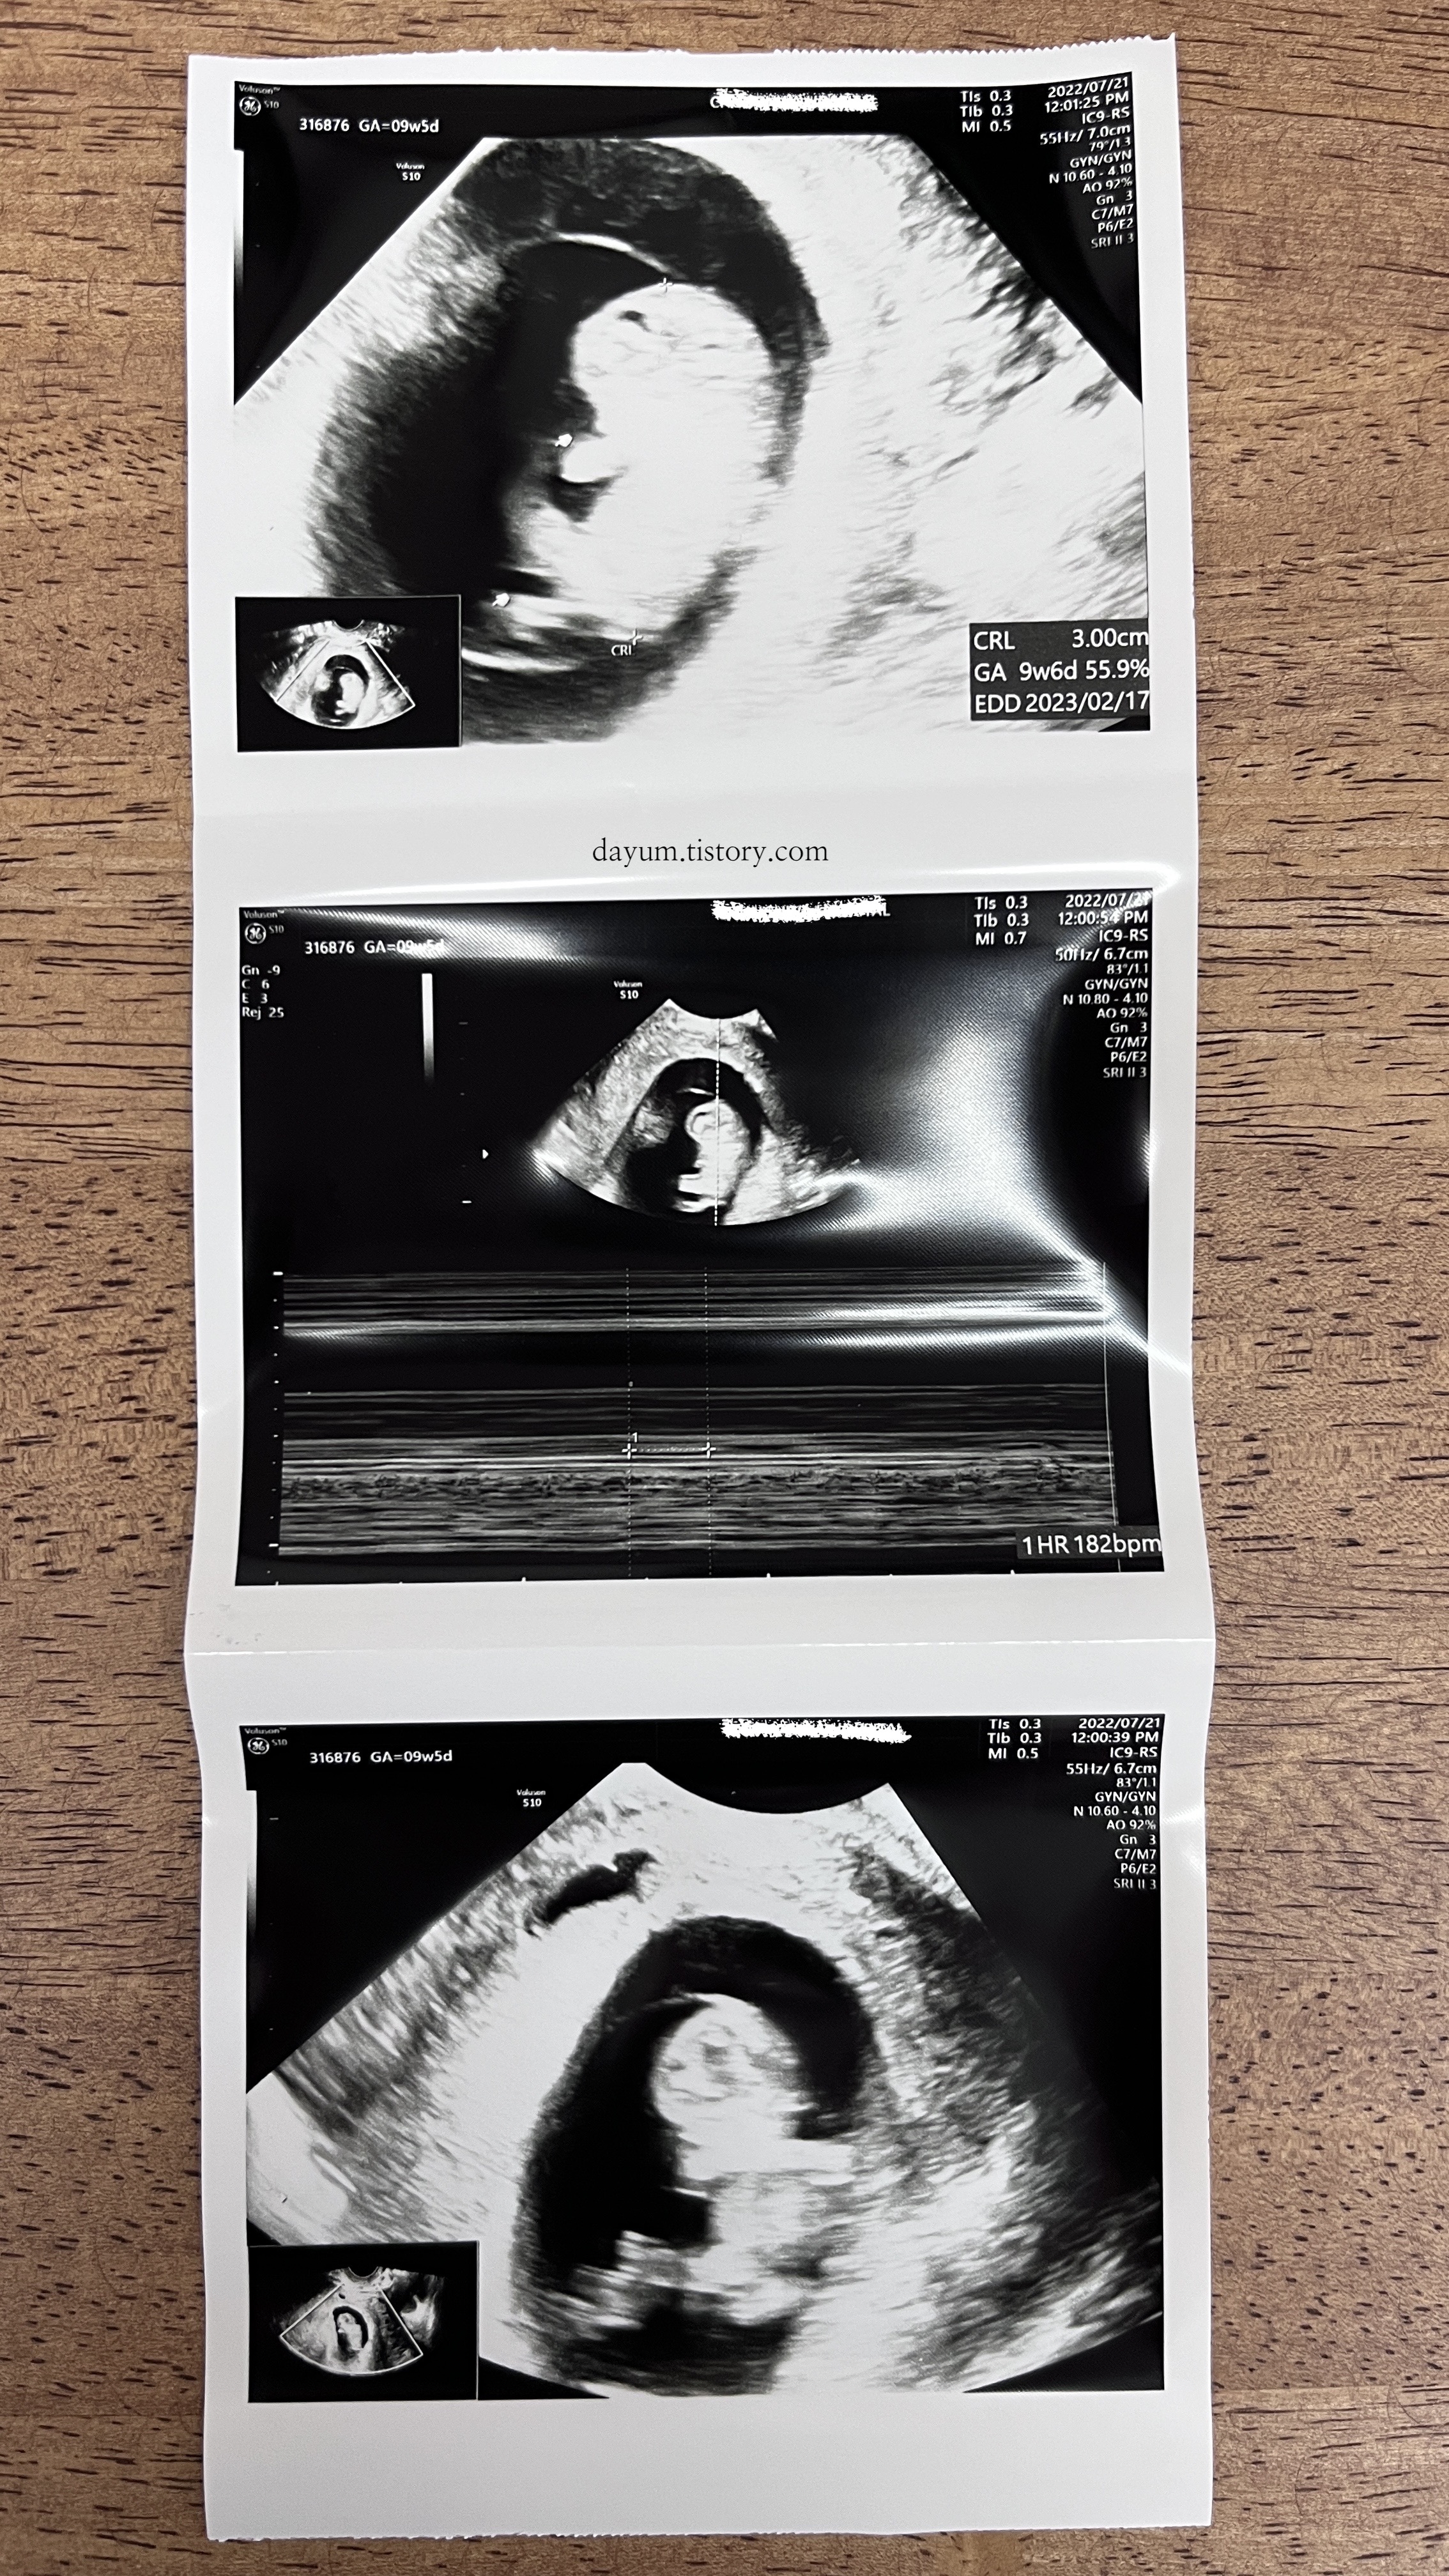

초음파 화면은 여전히 먼저 보지 못했다. 원장님이 뭐라 말씀하시면 그제서야 보게된다.

그동안 7mm 자랐다. 심박수는 182bpm인데 심장소리를 듣는게 태아에게 무리가 된다고 해서(초음파는 상관없음) 오늘은 소리는 듣지 않고 심박수만 체크했다. 많던 피고임은 아주 작게 하나가 남아있는데 위험한거는 아니라서 이제 눕눕 생활도 끝이다.

오늘은 아기가 손발도 흔들흔들 해주었고, 열심히 꼬물거려서 귀여웠다.

저번에는 탯줄이 생겼었고, 이제는 탯줄도 연결이 다 되었다고 한다.

뇌도 양쪽 대칭으로 잘 만들어졌다.